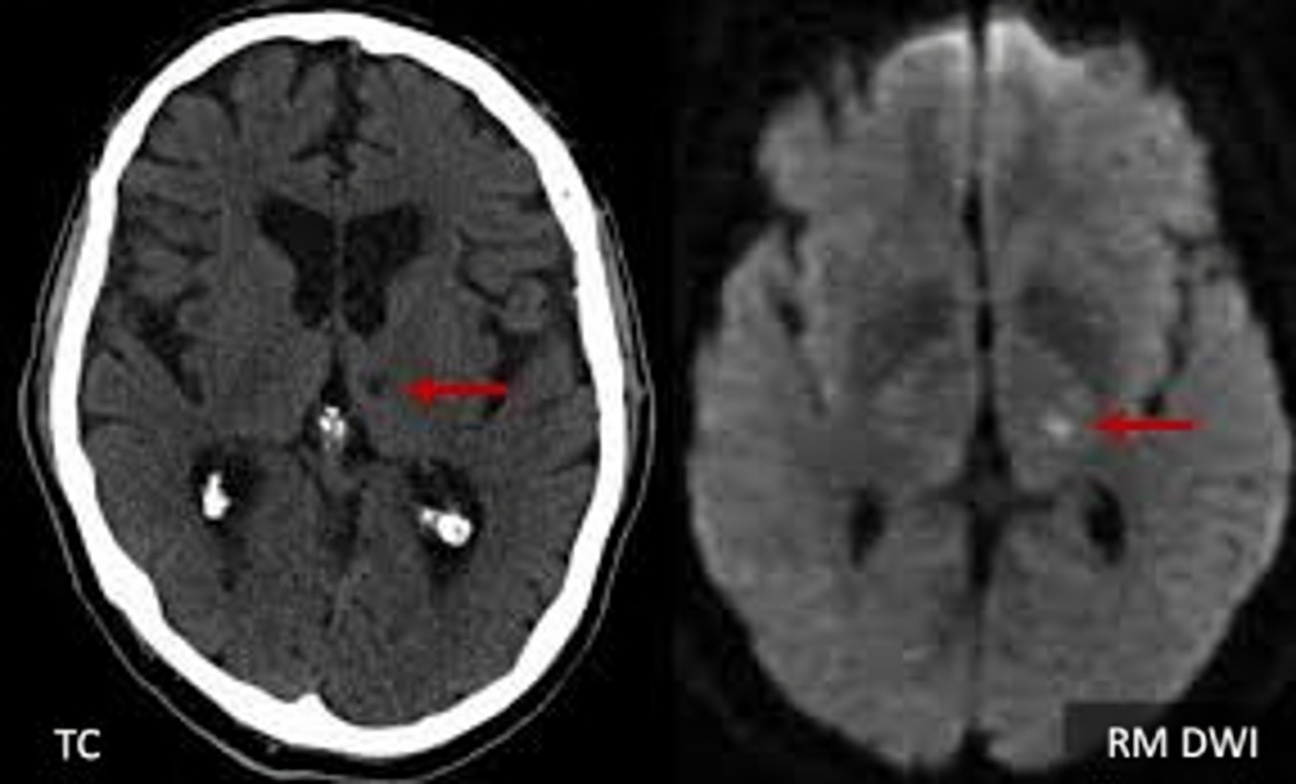

O AVC lacunar ocorre quando artérias minúsculas (algumas com diâmetro comparável ao de um fio de cabelo) ficam obstruídas dentro do cérebro. Diferentemente dos AVCs maiores, ele nem sempre causa sintomas dramáticos no início. Estudos relatados em publicações como Stroke e Neurology indicam que 20% a 30% dos adultos acima de 60 anos podem apresentar evidências de AVCs lacunares “silenciosos” em exames de imagem, mesmo sem sentir nada fora do comum.

Quando esses eventos se repetem, podem surgir pequenas cavidades (lacunas) em áreas essenciais como gânglios da base, tálamo e tractos de substância branca. A soma dessas lesões tende a afetar:

Imagem cerebral Pequenas lacunas e alterações de substância branca Alterações mínimas Padrões distintos (atrofia, placas, etc.)